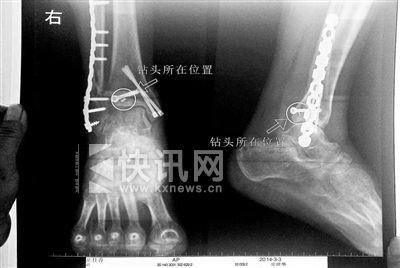

胡女士的腿部X光图 胡女士的腿部X光图

导读:看着X光片中自己腿内的异物,胡女士就感到莫名的担忧。胡女士于2013年3月在北京市丰台区右安门医院进行了一次骨折手术,术后医生才发现手术时用来打眼用的钻头不慎遗留在了胡女士的骨头中,并且无法取出。

“我当时就吓蒙了,怎么会有一个钻头在骨头里?”胡女士余悸未消地说,第二天拍摄的X光片显示,2厘米左右的钻头遗留在她右脚脚踝上部的骨头内。

“按照照片里的位置,相对来说是没有害的。”丰台区右安门医院医务科徐主任告诉胡女士,任何事情都无法做出绝对的判断,但是从目前情况而言,钻头对于腿部没有更多的危害。她介绍说,临床上遇到过很多这种情况,诸如钢板钉子,有时候钉子滑扣,无法取下,也只能存在体内,但是这些都是个别情况。

“留在她腿里的钻头确实无法取出。”徐主任解释说,按常理说,钻头不应该断在里面,但现在事情确实发生了。钻头没有折在关节,而是在跖骨内,跖骨主要起支撑作用,不像关节那样起活动作用,而且这个部位比较质密,并非像肌肉要经常活动受到挤压。